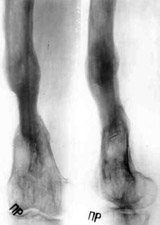

Patient in Ilisarov's apparatus.Patient in Ilisarov's apparatus.Patient in Ilisarov's apparatus.

Patient in Ilisarov's apparatus.